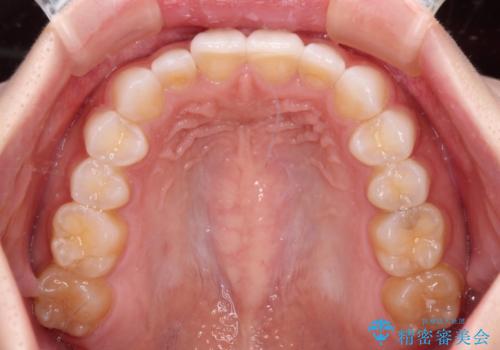

- 矯正治療で歯列を整えた後、前歯の形が気になった患者様です。

矯正前の歯列の影響で、前歯の先端が非対称にすり減ってしまったため、矯正治療後の形が非対称になっていました。

むし歯はなく、矯正治療で咬み合わせが改善していたので、侵襲量の少ないラミネートベニアにて治療することとしました。